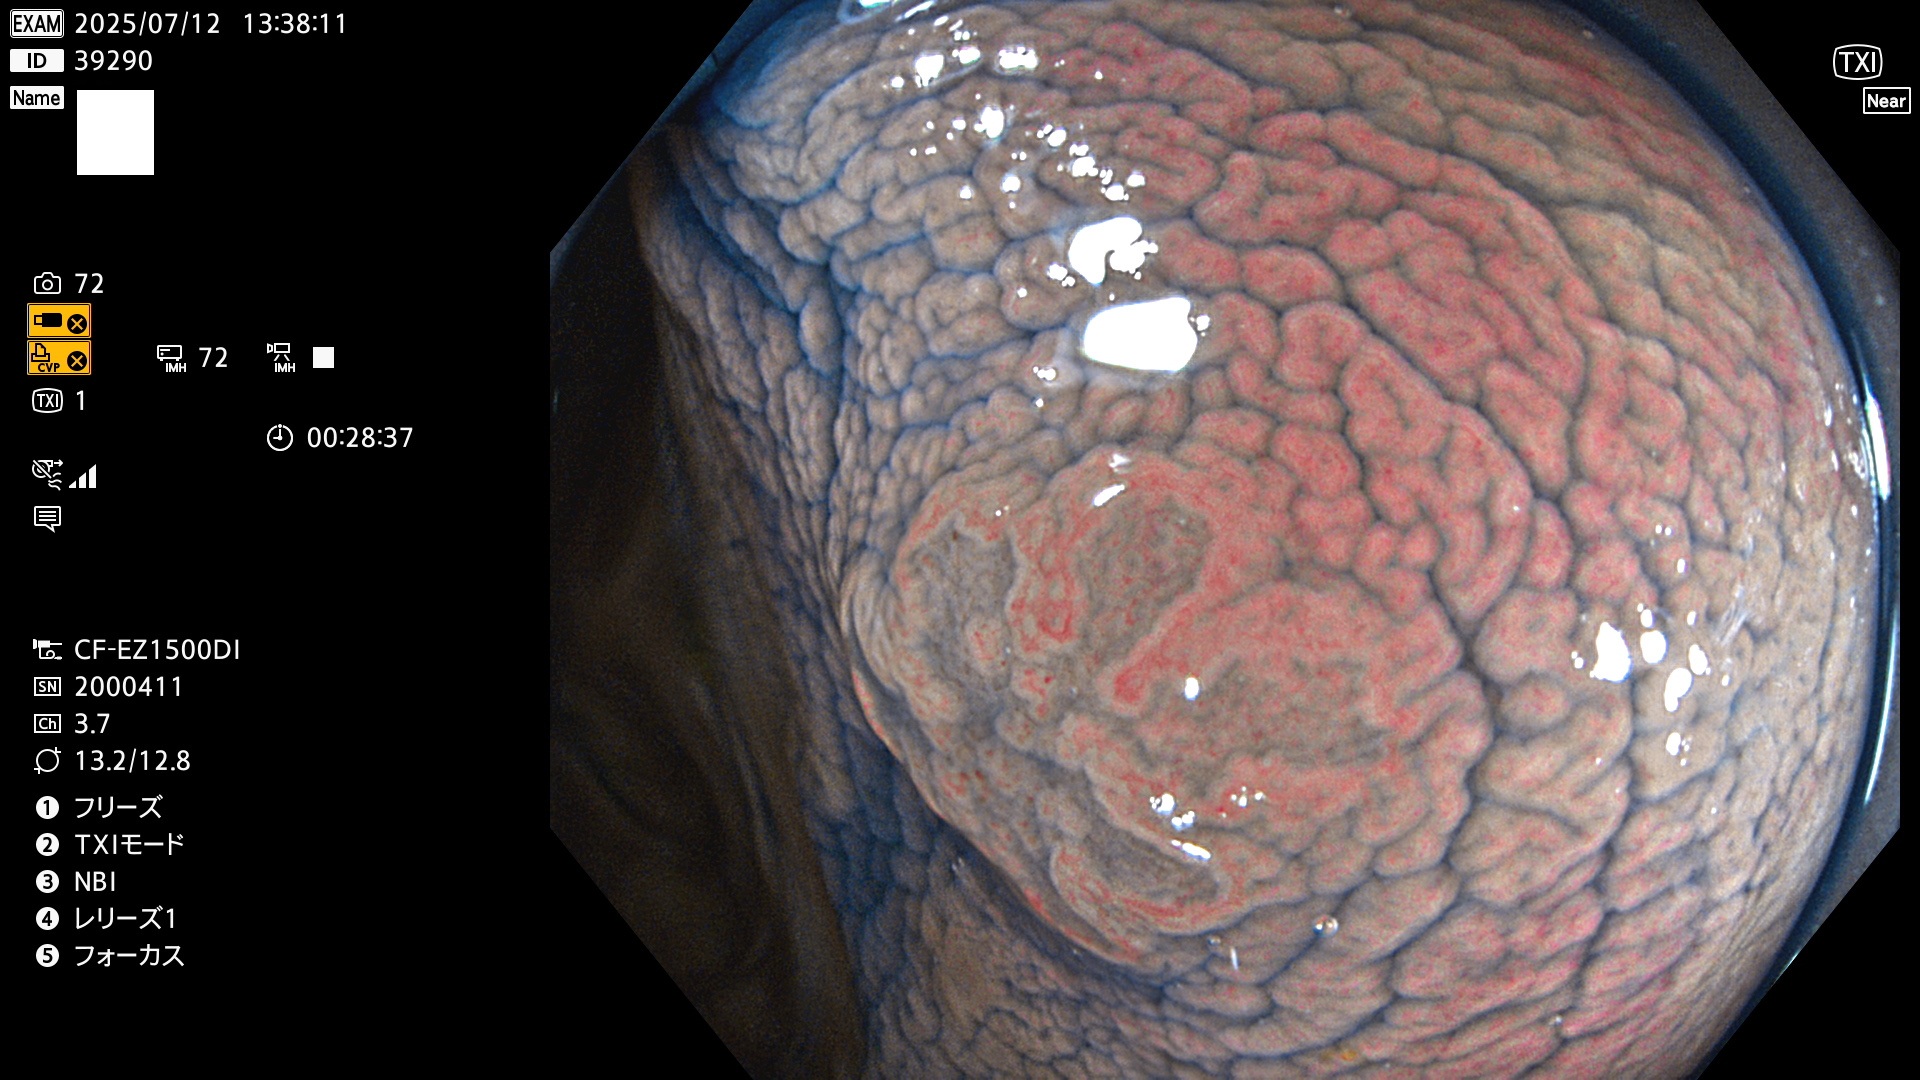

2025年7月10日〜7月13日の4日間(40件)15個 (Uc_ADR=15/40=38%)